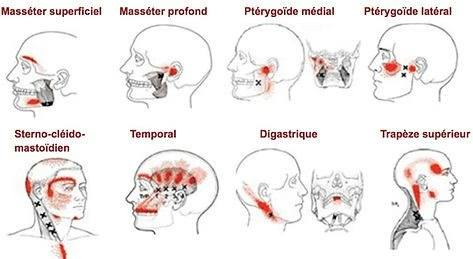

- Syndrome myofascial (bruxisme, serrement) : sur-utilisation musculaire créant des points gâchettes douloureux

L'ostéopathie réduit les tensions musculaires liées au bruxisme (muscles masséters, temporal, ptérygoïdiens) et peut diminuer la fréquence des épisodes. Elle ne traite pas la composante psychologique du bruxisme, pour laquelle la TCC est recommandée.